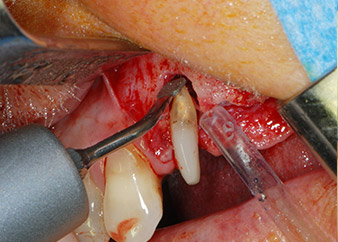

Einen Monat nach dem Eingriff waren sowohl die Schmerzen als auch die Entzündung an Zahn 24 minimal, die Zahnbeweglichkeit lag jedoch noch bei Miller-Klasse 2. Nach Freilegung und Reinigen des infizierten periapikalen und periradikulären Gewebes wurde das Ausmaß des Knochendefizits deutlich (Abb. 2 und 3).

An der bukkalen Wurzel fehlte der gesamte vestibuläre und distale Knochen. Das Attachment beschränkte sich weitgehend auf die palatinale Wurzel, was die anfängliche schlechte Prognose unterstreicht. Auch Zahn 27 wies ein verringertes horizontales Attachment (vgl. Abb. 12) und eine kleine apikale Aufhellung (Abb. 1) auf, allerdings ohne klinische Symptome.

Abb. 2 und 3: Bei der Freilegung einen Monat nach endodontischer Revision und Beginn einer systematischen Parodontalbehandlung weist die bukkale Wurzel des Zahns 24 einen kompletten Verlust von Knochen und Attachment auf.

Zunächst wurde in einem Versuch, das Paro-Endo-Problem zu lösen, an der verbleibenden Wurzeloberfläche ein vorsichtiges Debridement mit einem piezochirurgischen Gerät vorgenommen (Piezomed, W&H) (Abb. 4); dann wurde der Apex mit dem gleichen Instrument im Sinne einer WSR abgetragen, um das verbleibende infizierte apikale Gewebe zu entfernen (Abb. 5). Eine retrograde Füllung war nicht notwendig, da die orthograde Füllung gerade revidiert worden war.